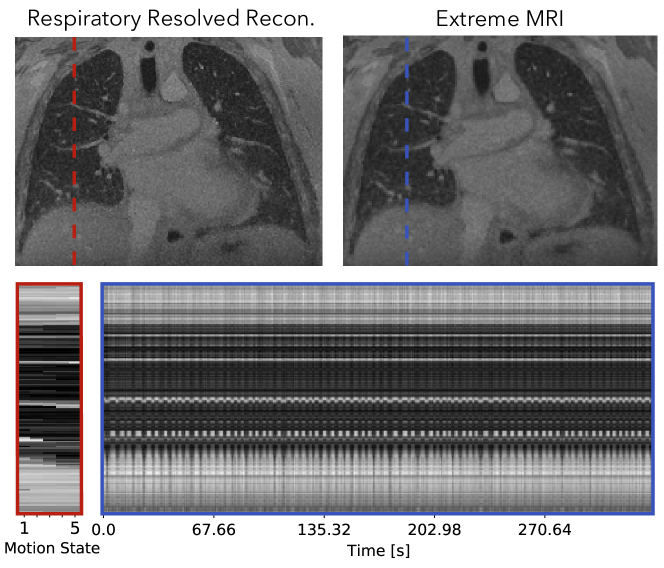

Figure 10 and Supporting Information Video S13 and S14 compare the proposed method with the respiratory-resolved reconstruction. From the cross-section and Supporting Information Video S13, coughing can be observed in the beginning of the scan for the proposed reconstruction. The patient can be seen to return to a more regular breathing pattern after a while but still occasionally show abrupt motions. The proposed reconstruction does show flickering temporal artifacts when the patient coughs, but in general has less noise-like artifacts and much sharper features than the respiratory resolved reconstruction.

Refer to caption

Figure 10: Comparison of the proposed method with the respiratory-resolved reconstruction of the second lung dataset. Dynamics can be seen more clearly in Supporting Information Video S13 and S14. From the cross-section and Supporting Information Video S13, coughing can be observed in the beginning of the scan for the proposed reconstruction. The patient can be seen to return to a more regular breathing pattern after a while but still occasionally show abrupt motions. The proposed reconstruction does show severe flickering temporal artifacts when the patient coughs, but in general has less noise-like artifacts and much sharper features than the respiratory resolved reconstruction.

Figure 10 shows that for pulmonary imaging, the proposed reconstruction really shines when there are non-periodic motions. Because Figure 9 mostly consists regular breathing, the proposed reconstruction does not offer much beyond unrolling the periodic dynamics. However, for the second dataset with irregular breathing, the proposed reconstruction provides substantially improved image quality, and also depicts the irregularities. In particular, coughing can be seen from the beginning of the dynamic image series.